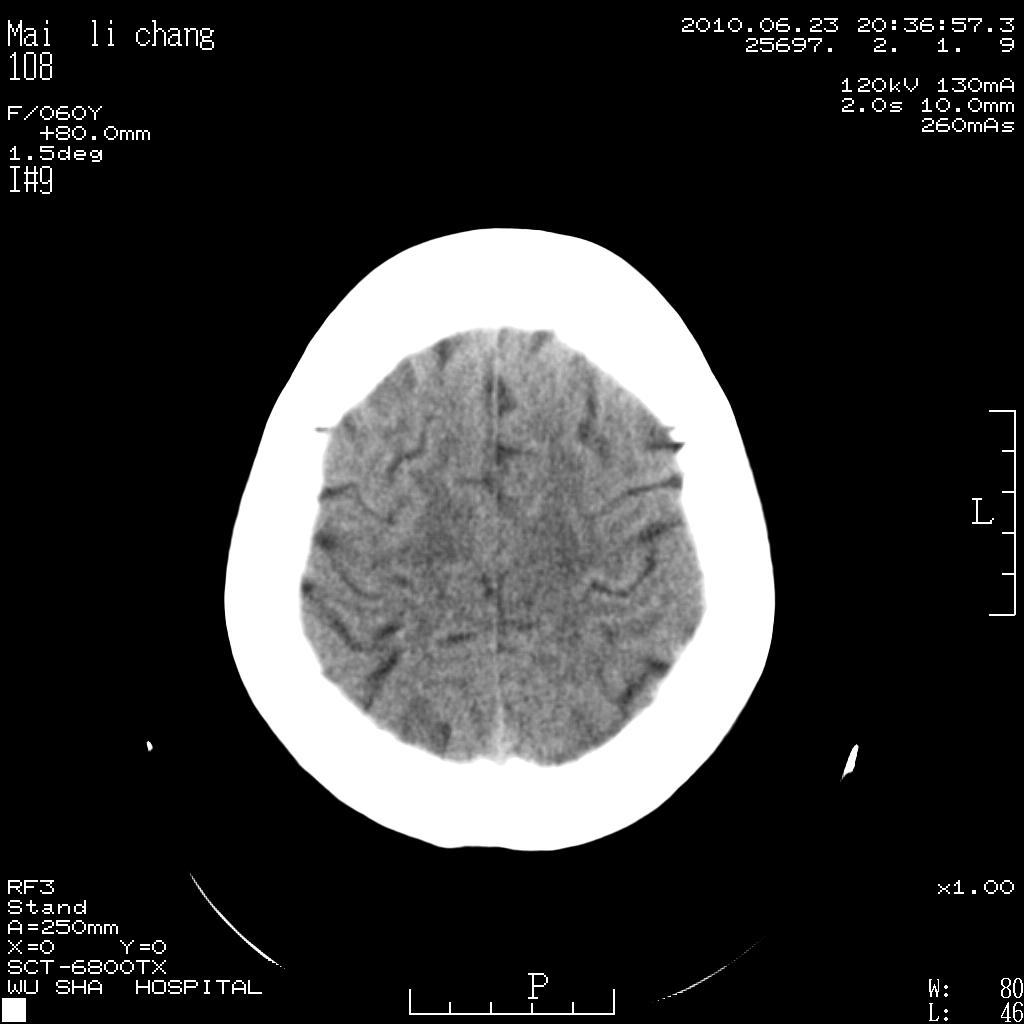

女性,60岁,右手无力一天

脑梗塞?并皮层下动脉硬化性脑病?还需要考虑什么?请大家指导,先谢了。

考虑左侧梗塞灶

左侧基底节区及放射冠区多发脑梗塞。

左侧基底节及放射冠区脑梗塞。